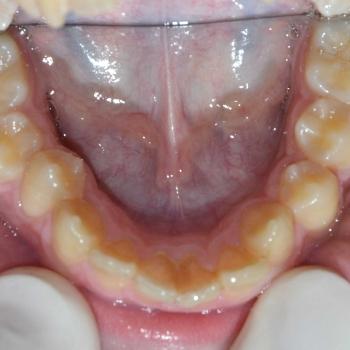

Balázs és édesanyja konzultáció céljából keresett fel, hogy egyértelműen kiderüljön számukra szükséges-e a fogszabályozó kezelés vagy sem. Már rögtön az első vizsgálat alkalmával fény derült több olyan problémára is, melyek fogszabályozást igényelnek. Ilyen volt például a súlyos mélyharapás, a hátrafelé dőlő felső metszők, illetve az Angle II. osztályú harapási eltérés is. A mintavétel, a röntgenek és a fotók kiértékelése után további problémaként merült fel a felső fogív szűkülete és a kismetszők méretaránytalansága, azaz a túlzott keskenységük.

A kezelést Quadhelix fogszabályozóval kezdtük el a felső fogív tágítása érdekében. Ezután került felragasztásra az alsó és felső fogívre a Balázs és szülei által kiválasztott fém önligírozó fogszabályozó. Ezen túlmenően Bite turbo harapásemelő segített a mélyharapás, intermaxillaris gumihúzás pedig az Angle II. osztályú harapási eltérés korrigálásában. A fogak méretaránytalansága miatt a kezelés végén a kismetszőket tömőanyaggal építettük fel, hogy a tökéletes harapáshoz résmentes fogazat társuljon. A fogak felépítéséhez az adott fogakat nem kell megfúrni, a tömőanyag kizárólag ragasztásos módszerrel rögzül, így nem károsodik a fogzománc.